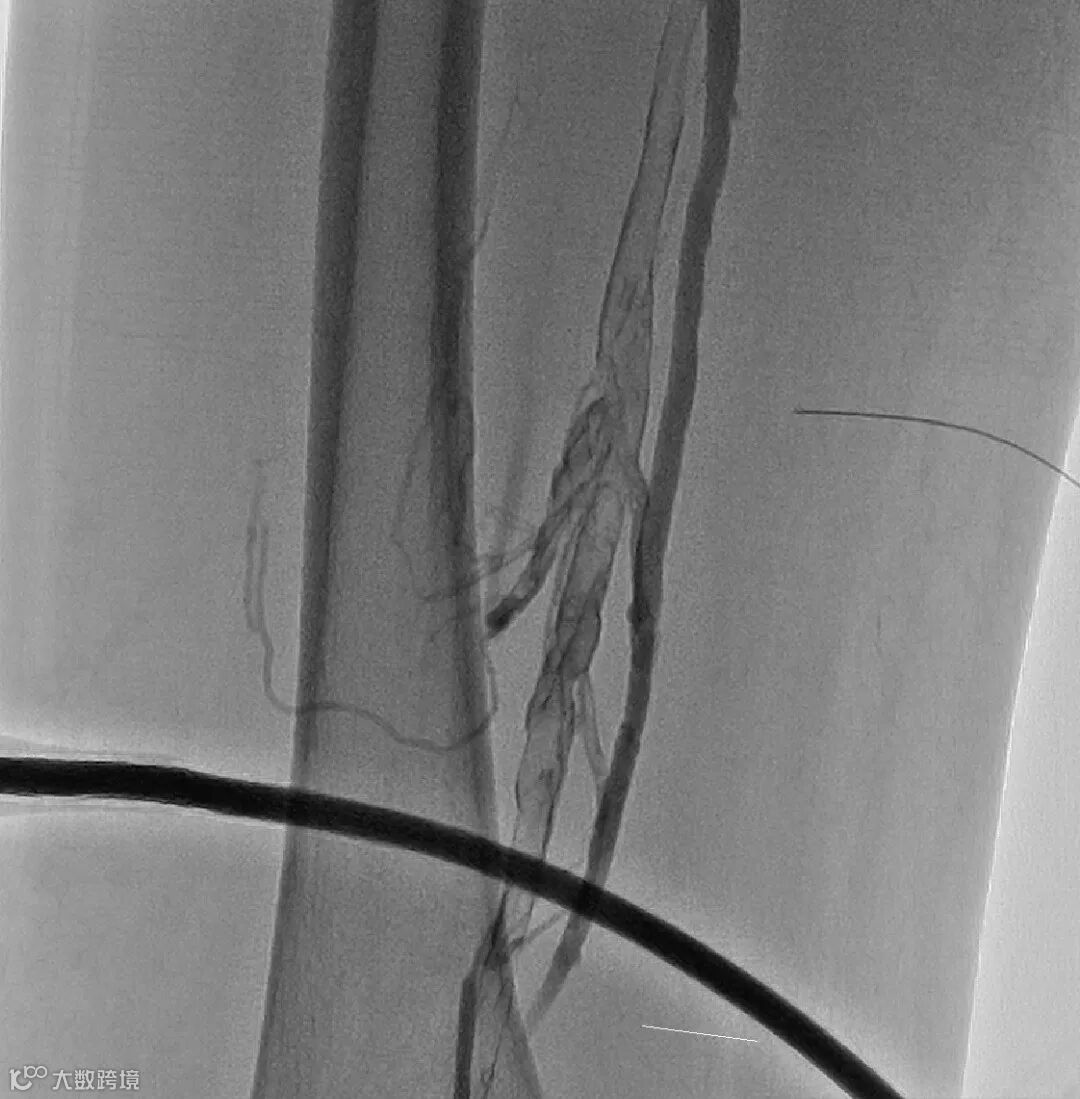

取出的血栓

4. 送入腾复Tendfast®外周静脉取栓支架,左股静脉拉栓1次,造影显示:左股静脉血流通畅。

6. 引入Tendfast®外周静脉取栓支架,从左侧髂静脉拉栓2次,造影显示血流恢复通畅。